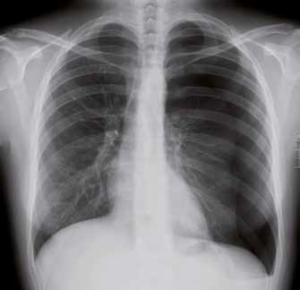

Quando si ha pneumotorace quello che accade è un abolizione delle vibrazioni vocali e delle murmore vescicolari, timpanismo alla percussione e iperclarità radiologica.

Da un punto di vista radiologico si apprezza iperchiarità dell’aria, il moncone di polmone e la deviazione del mediastino.